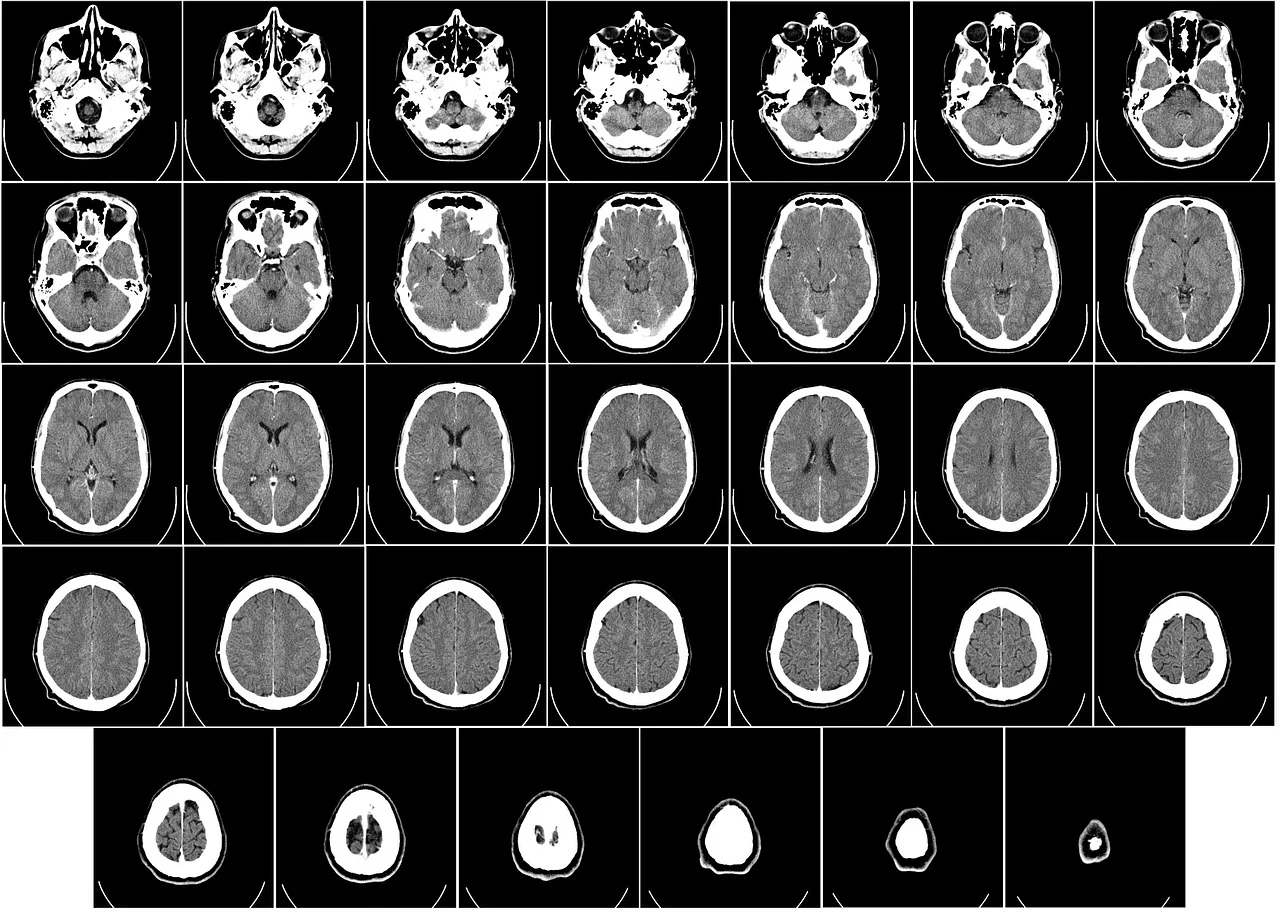

| X선·감마선 | <10nm | CT, 원자력, 천문학 관측 |

또한, 미래에는 의료용 전자기 기술이 확대될 것으로 예측됩니다. 이미 TMS(경두개 자기 자극), 전기 자극 치료기, RF 수술기 등에서 전자기파는 질병 치료에 직접 활용되고 있습니다.

✅ 의료·에너지 분야 확장

비침습 전자기 센서: 혈당 측정, 체온 탐지, 심박 측정

무선 에너지 전송 시스템: 전기차 무선 충전, IoT 기기용 에너지 하베스팅

나노전자기 기술: 암세포 열치료, 약물 전달용 RF 기술 등